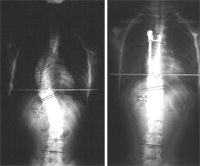

Cuando se observa la columna vertebral por detrás, la espalda parece recta, pero si se mira de lado se aprecian curvas. Estas curvas en el cuello (lordosis cervical), región torácica (cifosis torácica) y región lumbar (lordosis lumbar) son normales y se necesitan para mantener un equilibrio apropiado del tronco sobre la pelvis y proteger a las estructuras vertebrales de las cargas. Desviaciones de este alineamiento normal pueden producir una deformidad en cifosis, deformidad en lordosis, o una escoliosis.

La palabra escoliosis proviene del griego y significa curvatura lateral de la columna vertebral. Esta enfermedad se manifiesta clínicamente por la curvatura lateral de la columna, acompañada por la rotación de las vértebras afectadas.¿Por qué surge la escoliosis?